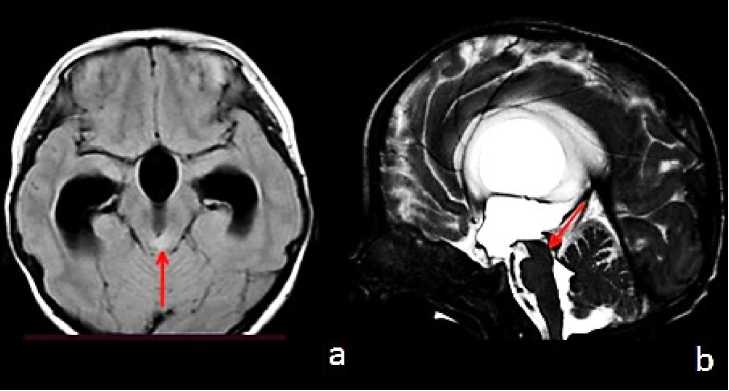

Для верификации уровня окклюзии ликворных путей выполнялось МРТ головного мозга с использованием фазово-контрастных последовательностей CSF_QF и прицельных тонкосрезовых сагиттальных сканов CSF DRIVE. На МР-изображениях определялся уровень блока ликворных путей, преимущественно на уровне Сильвиева водопровода (Рисунок 1).

Рисунок 1. МРТ головного мозга в режиме фазово-контрастной последовательности CSF_QF и тонкосрезовых сагиттальных сканов CSF DRIVE: A — аксиальный срез; B — сагиттальный срез. Красной стрелкой указана обструкция Сильвиева водопровода